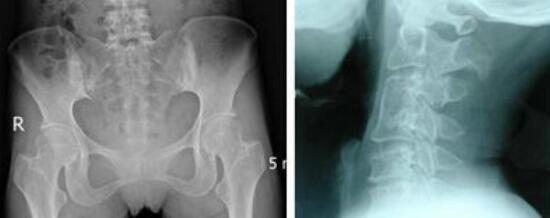

王怀庆主任根据张先生的临床症状和入院检查结果,确诊其患有晚期强直性脊柱炎。由于张先生的病情比较严重,王怀庆主任召开了临时会议为他制定了合适的治疗方案。 ...[详细]

刘先生经常感觉脖子痛、大腿内侧开始出现红肿现象,后来疼痛红肿症状加重。经附近医院检查,确诊为强直性脊柱炎,经过药物治疗无效后病情加重:脖子有时僵硬的都不能左右转动;大腿内侧的红肿也越来越严重,...[详细]